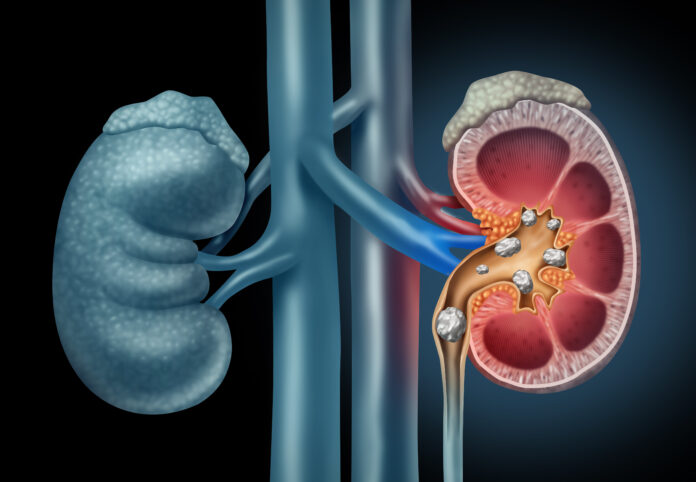

El dolor aparece sin aviso: inicia en la espalda, se extiende al abdomen y, en ocasiones, llega hasta la ingle. En muchos casos, se trata de cálculos renales, también conocidos como piedras en el riñón. Estas pequeñas acumulaciones sólidas, formadas por minerales y sales, pueden generar molestias intensas y, si no se tratan a tiempo, provocar infecciones o daños permanentes en el sistema urinario.

Qué son los cálculos renales y cómo se diagnostican

Los cálculos renales se forman cuando ciertas sustancias presentes en la orina, como calcio, oxalato o ácido úrico, se concentran y cristalizan. Su tamaño puede variar desde un grano de sal hasta una pelota de golf, y mientras más grandes sean, mayor es el riesgo de obstruir el flujo de orina.

El diagnóstico se realiza mediante análisis de orina y estudios de imagen, como ultrasonido, radiografía o tomografía computarizada, que permiten determinar el tamaño, ubicación y tipo de cálculo.